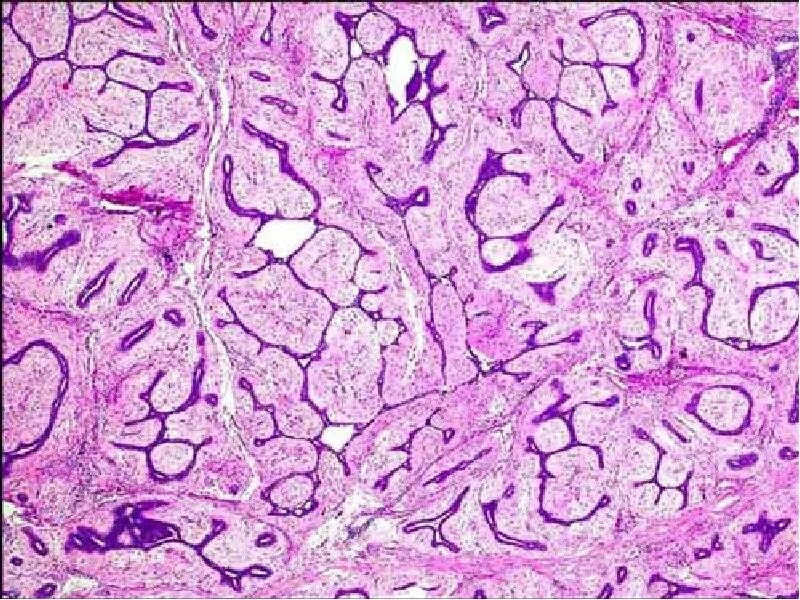

Фиброаденома гистология